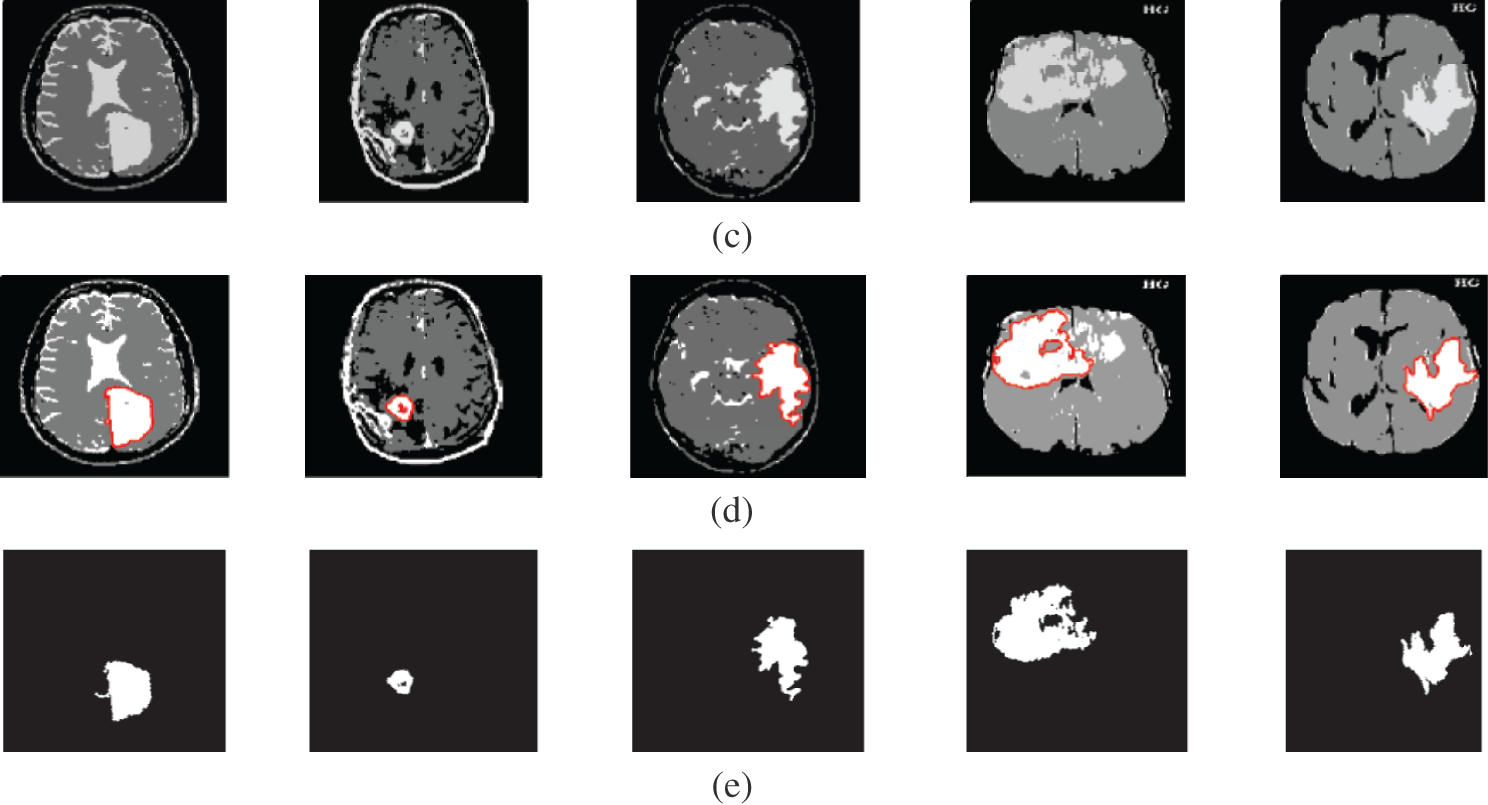

4 Noise Effect on the Segmentation Process

It is well known that the histogram can describe the distribution characteristics of image data. It is simple to perform segmentation if the histogram has a number of peaks. Speckle noise with 0.05 variance was added to the Us images, and Gaussian noise with 0 mean and 0.02 variance was added to the other image modalities. The original image histogram has one or two obvious peaks on contrary to the noisy image histogram, which has no obvious peaks. Fig. 7 shows a comparison of distribution characteristics of image data for the original image and noisy image.

Figure 7: Comparison of distributions of data for original images and noisy images (a) Original images (b) The original images histograms, (c) Noisy images, and (d) Noisy images histograms

It is shown that the proposed approach can achieve average segmentation accuracies of 0.9813, 0.9964, 0.9992, 0.9858, and 0.9892 for Us, mammogram, CT, PET, and MRI images. Furthermore, results show good accuracy and similarity results for the noise-free and noisy images. Obviously, combining morphological operation with the FCM algorithm can improve the distribution of the image data and facilitate the segmentation process. In addition, morphological operations can maintain the object boundaries and eliminate the noise effect. The proposed technique has low complexity, as shown in Tab. 12. It is easy to obtain good results for image segmentation with the introduction of membership and morphological operations filtering. The illustrated results show that the proposed technique can segment and extract the tumor region successfully even in the presence of different noise types.